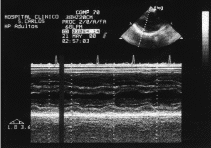

A su llegada a urgencias estaba consciente y orientado (GCS 15), con presión arterial de 110/85 mmHg, frecuencia cardíaca de 116 lat/min, frecuencia respiratoria de 20 resp/min y saturación arterial de oxígeno (pulsioximetría) del 95%. En la exploración se apreciaba una herida incisa de 2 cm en la región submamaria izquierda, que no sangraba hacia el exterior. En la auscultación pulmonar había una ventilación normal en ambos hemitórax y en la auscultación cardíaca los tonos eran rítmicos, sin roce ni soplo. El abdomen era blando y depresible, sin defensa abdominal. No había alteraciones en las extremidades. En la radiografía de tórax no se advertían signos de neumotórax o hemotórax. Se realizó una ecocardiografía transtorácica (fig. 1) que evidenciaba la presencia de un pequeño derrame pericárdico posterior y dilatación de la vena cava, que no colapsaba en la inspiración. Una ecografía abdominal no objetivó la existencia de líquido libre intraperitoneal. Durante la realización de todas estas exploraciones no se modificó el estado hemodinámico del paciente, y se infundieron otros 300 ml de cristaloides.

Fig. 1. Ecocardiografía transtorácica que evidencia un derrame pericárdico posterior.